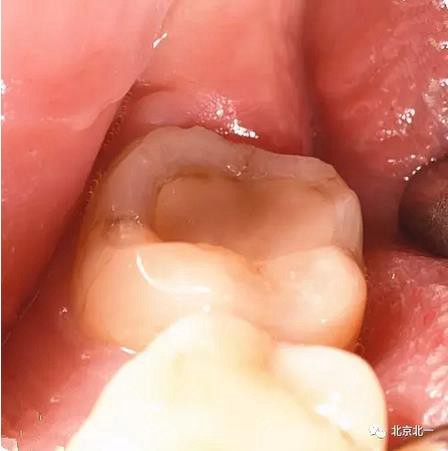

病例資料:一般情況,患者女性,28歲, 主訴:要求拔右側(cè)下頜智齒,檢查:右側(cè)下頜第三磨牙未見萌出, 拍片如圖。

圖五:臨床所見